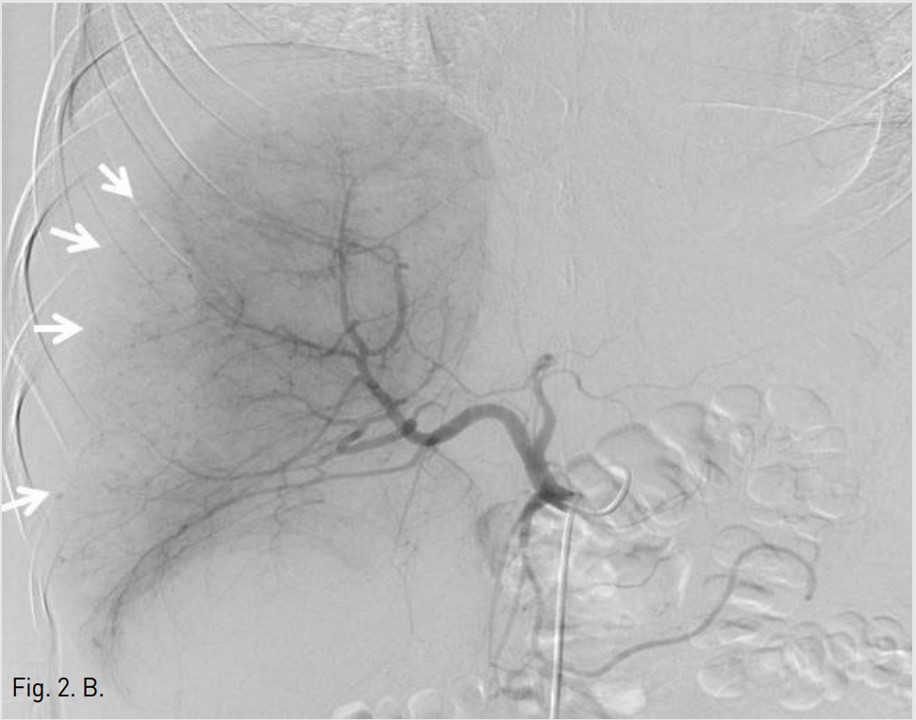

응급실에서 시행한 복부 CT검사에서 복강내 출혈 및 간 우엽의 후면을 따라 국소성 피막하혈종이 보였고, 내부에 출혈을 시사하는 조영제 유출이 보였다(AAST[American Association for the Surgery of Trauma] gradeⅡ)(Fig. 1A).

Fig. 1. A

Fig. 1A. Initial coronal CT scan shows a large subcapsular hematoma (arrows) with extravasation of contrast media (open arrow) inferior to the right hepatic lobe and perihepatic fluid collection, indicating hemoperitoneum (arrowheads).